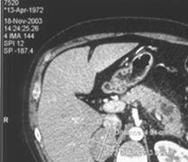

На рис.8 представлены изображения снятые при неудачном (слева) и правильном

(справа) выборе параметров съемки.

Рисунок 8

-Изображения, полученные при разных значениях параметра съемки.